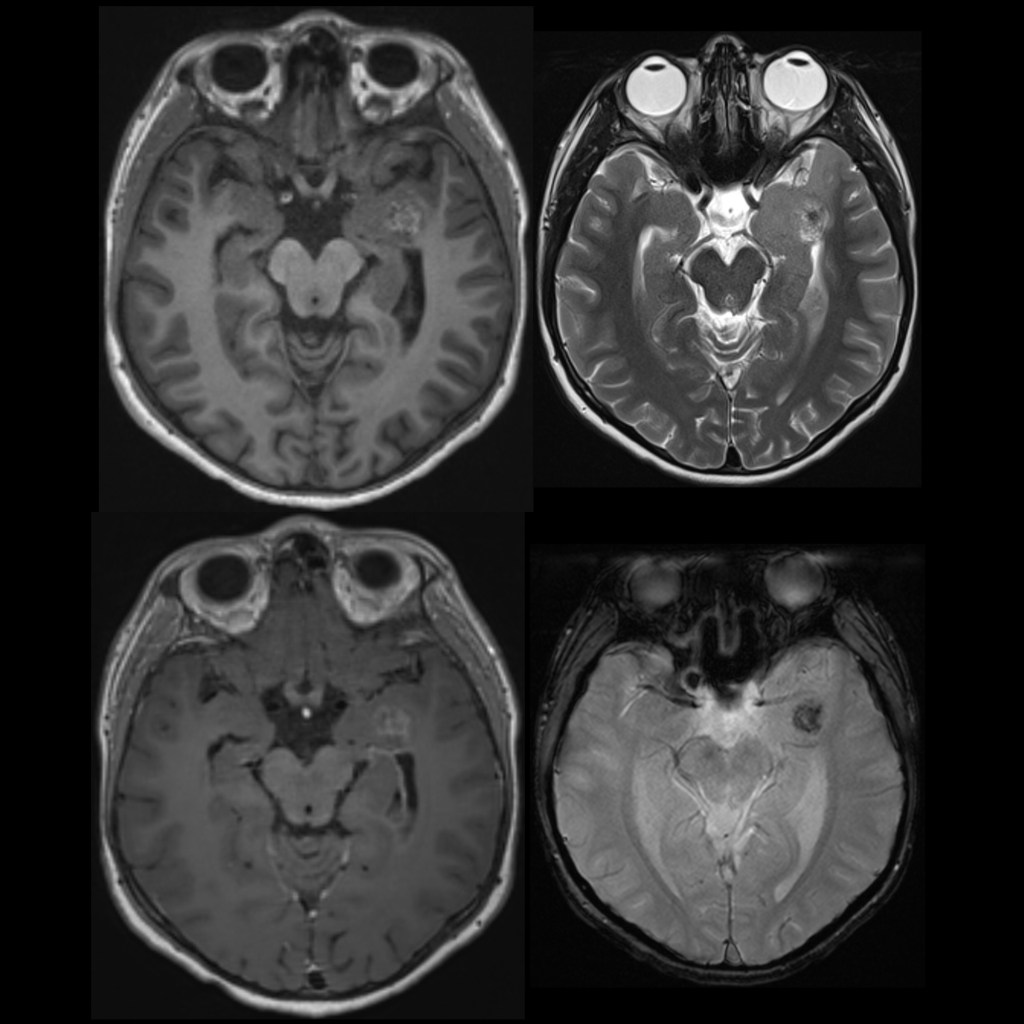

Dr Balaji Anvekar FRCR: DNET MRI

Dysembryoplastic neuroepithelial tumor (DNET) in a 19-year-old male ...

Roentgen Ray Reader: Dysembryoplastic Neuroepithelial Tumor (DNET)

Dr Balaji Anvekar FRCR: Dysembryoplastic Neuro Epithelial Tumor (DNET)

Dysembryoplastic neuroepithelial tumor (DNET) - Neuro MR Radiology Case ...